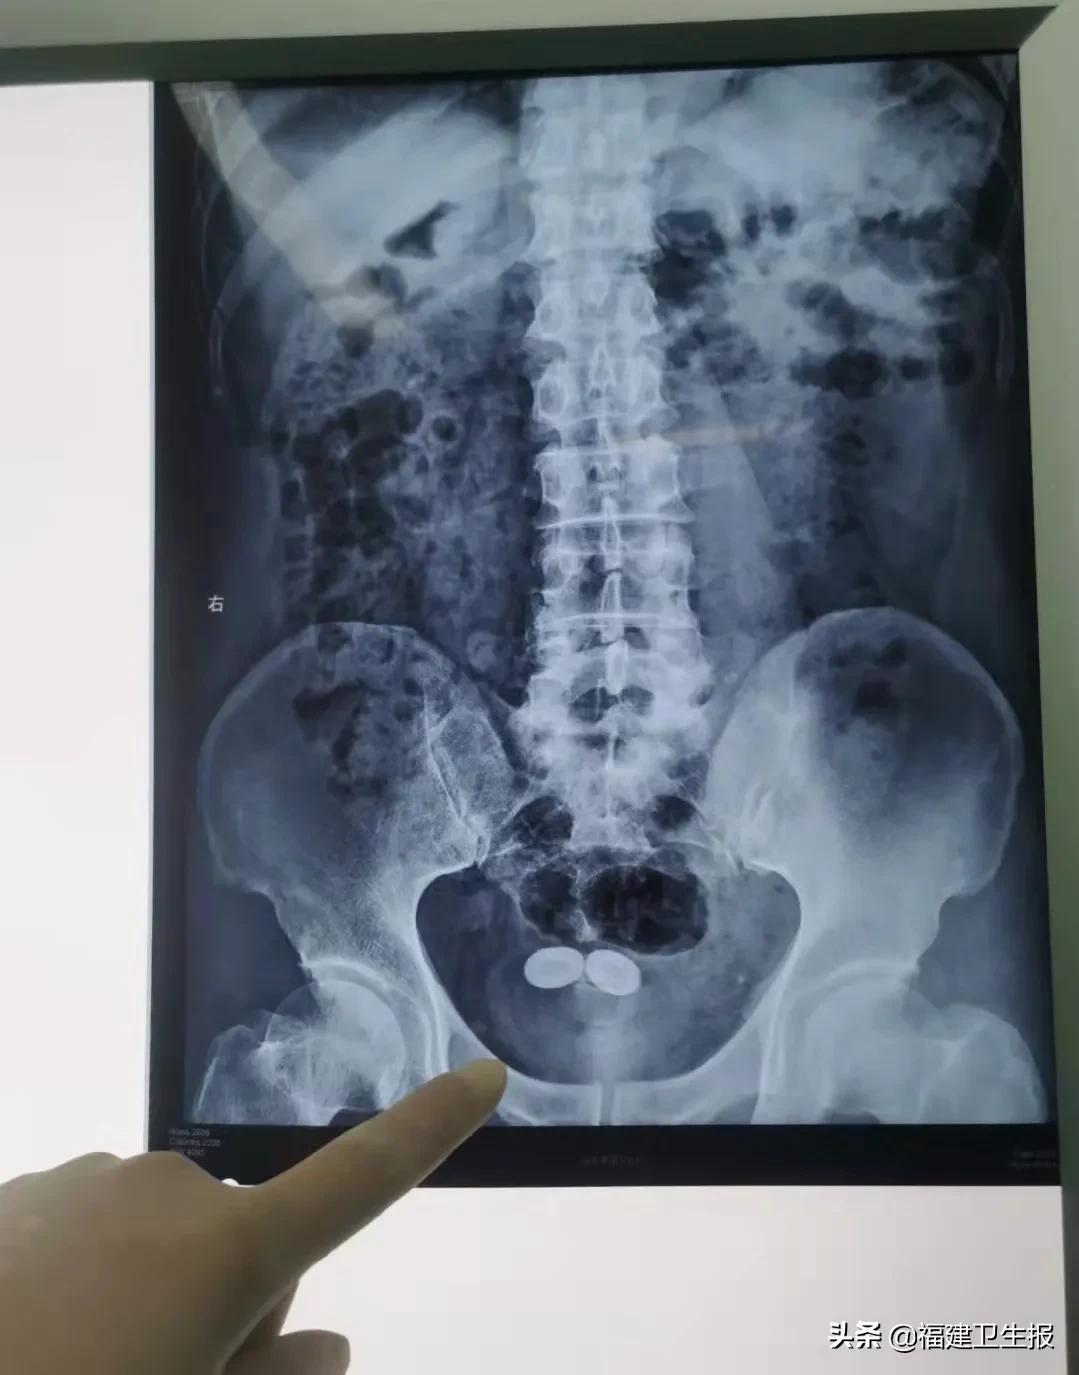

近来,他排尿时还出现了疼痛,不得不去医院就诊。检查发现,陈大爷的前列腺体积已达到60ml。

且因为长期尿液排不尽,尿液中的成分沉淀,在陈大爷的膀胱里结块形成两个2公分大的膀胱结石。